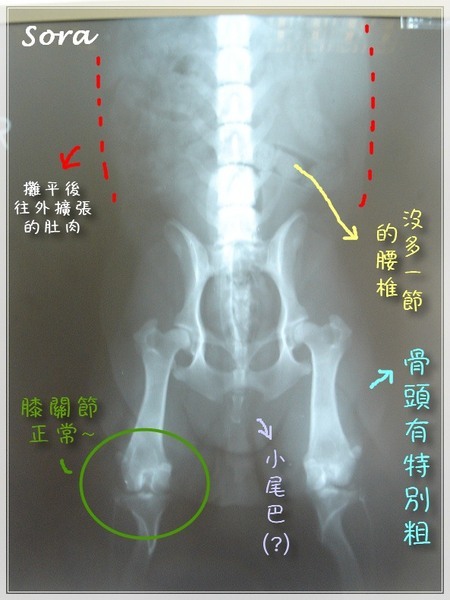

Lafy-CHD診斷結果說明這次CHD的檢查重點就是

1.髖關節窩和股骨頭的包覆狀況(鬆弛度)→搜拉輕度

2.有無出現二次退化性關節炎→搜拉正常

3.身長特別長的狗腰椎有沒有多一根(從肋骨最下面開始數正常共7根)→搜拉正常

(不知道腰椎多一節這個問題的人,請至病狗繁殖 犬基因突變跛腳腰椎多1節看一下)

以下是搜拉的報告第一張:(點進圖片看清晰版)

搜拉的報告第二張:分四階段來看吧(點進圖片看清晰版)

再一次放上搜拉X光片